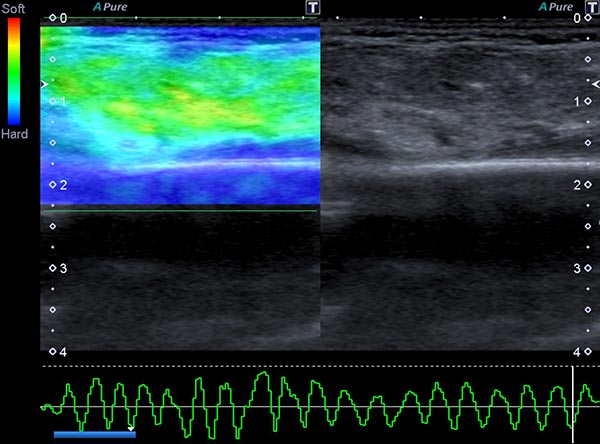

In der Ultraschall-Elastographie kann die mechanische Härte des Tumors farbkodiert dargestellt werden (links im Bild), rechts im Bild das zugehörige B-Bild. In der Farbkodierung wird hartes Gewebe blau dargestellt, mittelhartes grün und weiches Gewebe rötlich. Der Tumor selbst ist mittelhart bis eher etwas weicher (grün) als das umgebende Gewebe (blau).